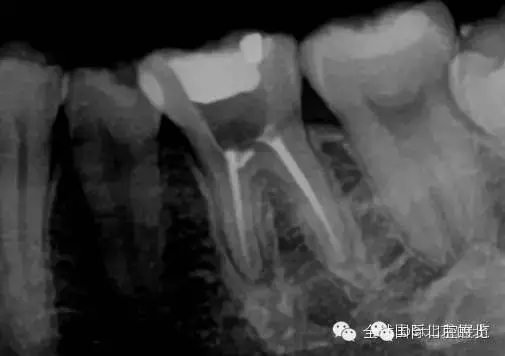

常規(guī)X-RAY全景片檢查

我們再來看看患牙:

X-RAY示:近遠(yuǎn)中牙根都有陰影存在,牙周膜都有些許增寬,近中頸部位置牙體有低密度減低影,就是楔狀缺損的位置。